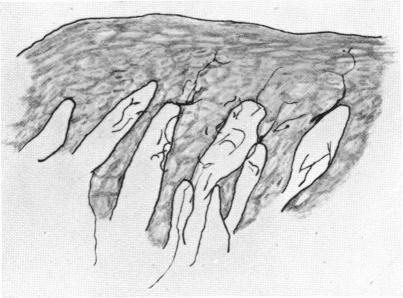

The Innervation of the Human Gum.

J Anat. 1938 Jul;72(Pt 4):531-534.3.